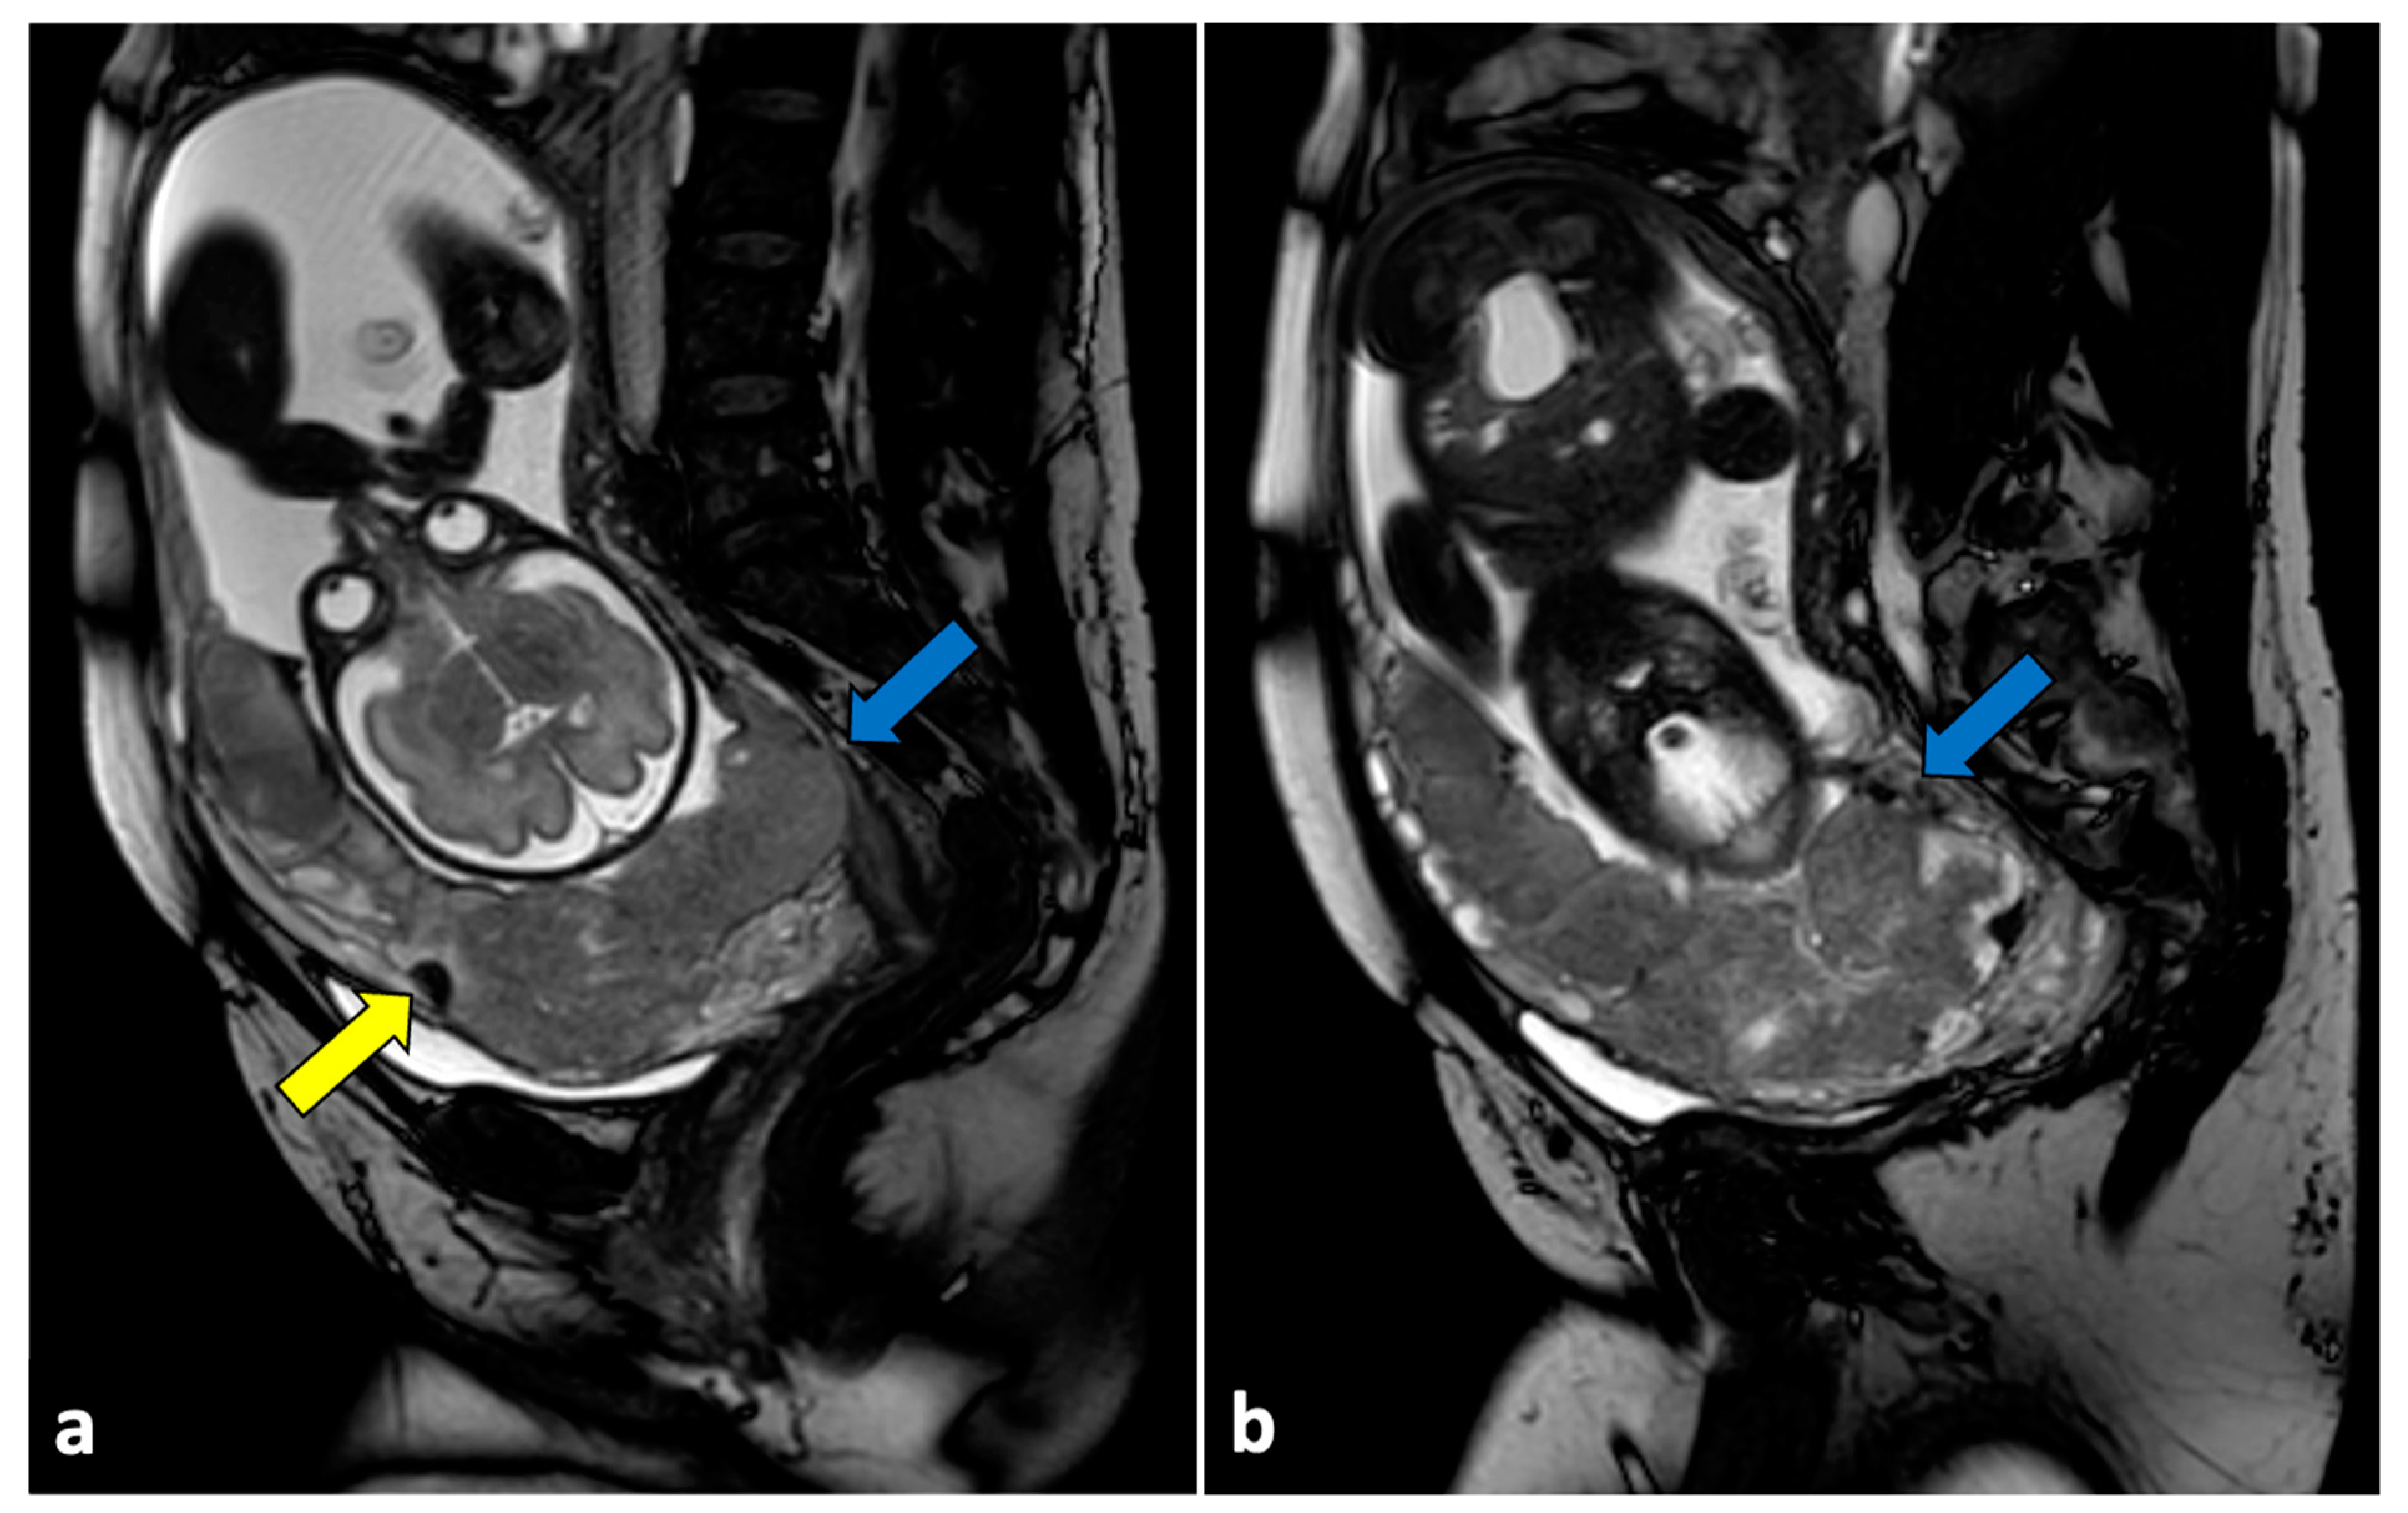

2.12. Placental Disorders

- Fadl, S.A.; Linnau, K.F.; Dighe, M.K. Placental Abruption and Hemorrhage-Review of Imaging Appearance. Emerg. Radiol. 2019, 26, 87–97. [Google Scholar] [CrossRef]

- Kilcoyne, A.; Shenoy-Bhangle, A.S.; Roberts, D.J.; Sisodia, R.C.; Gervais, D.A.; Lee, S.I. MRI of Placenta Accreta, Placenta Increta, and Placenta Percreta: Pearls and Pitfalls. Am. J. Roentgenol. 2017, 208, 214–221. [Google Scholar] [CrossRef]

- Kumar, I.; Verma, A.; Ojha, R.; Shukla, R.C.; Jain, M.; Srivastava, A. Invasive Placental Disorders: A Prospective US and MRI Comparative Analysis. Acta Radiol. 2017, 58, 121–128. [Google Scholar] [CrossRef]

- Donovan, B.M.; Shainker, S.A. Placenta Accreta Spectrum. Neoreviews 2021, 22, e722–e733. [Google Scholar] [CrossRef]

- Berkley, E.M.; Abuhamad, A. Imaging of Placenta Accreta Spectrum. Clin. Obstet. Gynecol. 2018, 61, 755–765. [Google Scholar] [CrossRef]

- Concatto, H.; Westphalen, S.S.; Vanceta, R.; Schuch, A.; Luersen, G.F.; Ghezzi, C.L.A. Achados Na Ressonância Magnética Do Espectro Do Acretismo Placentário: Ensaio Iconográfico. Radiol. Bras. 2022, 55, 181–187. [Google Scholar] [CrossRef] [PubMed]

- Weinstein, R.; Vaught, A.; Baras, A.; Gomez, E. Placental Bands on MRI in the Setting of Placenta Accreta Spectrum: Case Report with Radiologic-Pathologic Correlation. Radiol. Case Rep. 2023, 18, 491–494. [Google Scholar] [CrossRef] [PubMed]